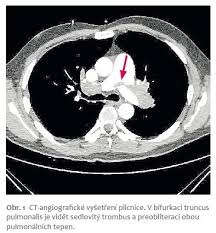

Plicní Embolie Rtg : Plicni Embolie Priciny Priznaky A Lecba Zdravi Euro Cz _ Ultrazvuk může zobrazit trombus v žilách dolních končetin, echokardiografické vyšetření může zobrazit přetížení pravé komory srdeční (v důsledku obstrukce plicnice).. Ultrazvuk může zobrazit trombus v žilách dolních končetin, echokardiografické vyšetření může zobrazit přetížení pravé komory srdeční (v důsledku obstrukce plicnice). Při zvažování diagnosy plicní embolie posuzujeme vedle klinických projevů přítomnost rizikových faktorů, laboratorní testy, ekg a rtg hrudníku.